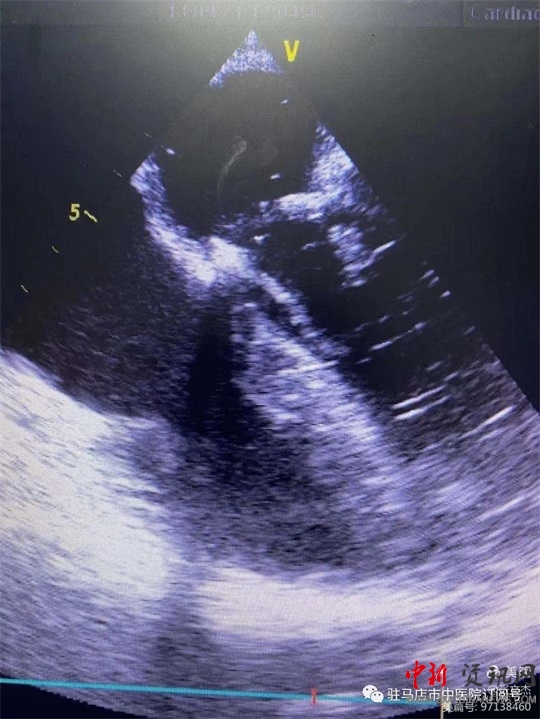

術(shù)前經(jīng)食道心臟超聲

復(fù)跳后經(jīng)食道心臟超聲,二尖瓣功能較術(shù)前明顯改善。